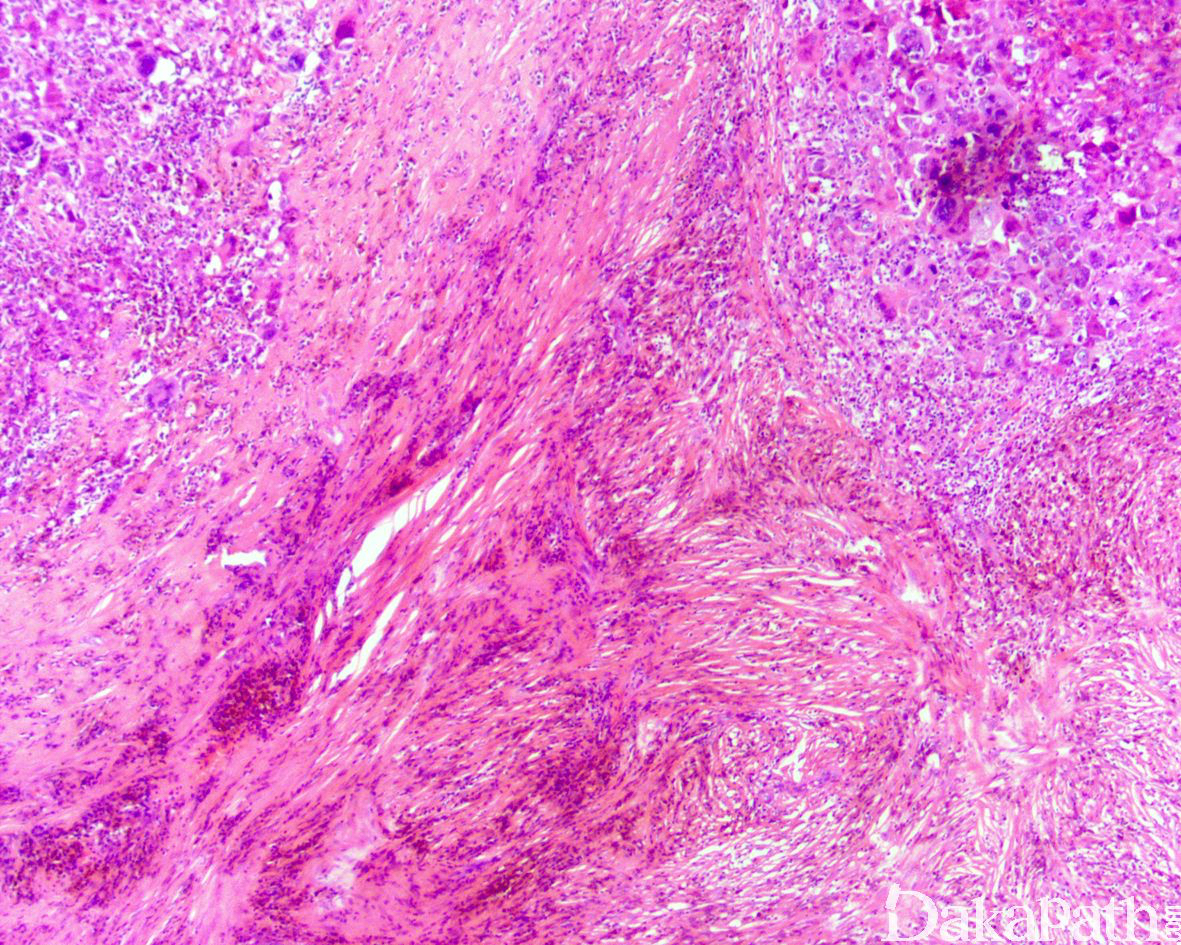

形态学与其他特殊类型的多形性肉瘤很相似,无一定的排列方式,常伴奇异的多核瘤巨细胞。

镜下细胞丰富,可见席纹状结构;

可见玻璃样变和坏死区域,也常见黄色瘤细胞;